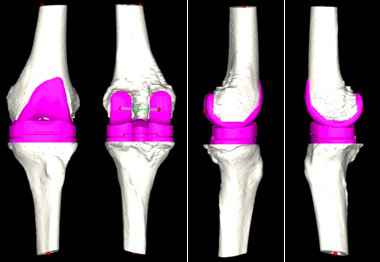

对此,张弛团队在与患者及家属充分沟通后,决定使用人工智能系统辅助置换全膝关节。专家在系统中上传患者的CT资料,人工智能便快速完成了术前规划,其模拟的假体型号及角度、位置十分精准。

人工智能术前规划模拟出精准的假体大小和位置。

“传统的全膝关节置换术极其依赖术中所见及骨科医生的临床经验,医生常需于术中反复比对以寻找最适假体大小,由于患者个体差异大、病情复杂等问题,导致全膝关节置换术后患者满意度偏低。”张弛解释说,“该患者病情复杂,通过人工智能辅助,能够在术前精准规划,帮助手术更快速、更精准的实现。”

8月20日,在手术室和麻醉科的密切配合下,张弛团队为患者顺利实施了左侧膝关节表面置换手术,术中发现膝关节严重磨损,大量痛风石堆积。由于术前人工智能的精准测量,使得手术步骤简化,耗时1个半小时就安装好假体完成了手术,整个手术出血不到30毫升。

术中运用后交叉韧带保留型的假体进行膝关节表面置换,术后复查照片精准复制了人工智能测量的结果。